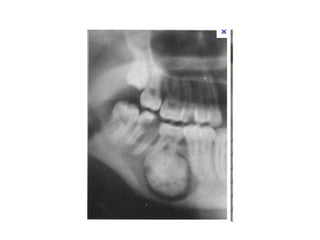

Ameloblastoma

• Ameloblastoma at the

angle of the mandible.

• Expansive form with

oval RL traversed by

few very thin septa

9

• More advanced case of ameloblastic fibroma

demonstrates how the follicular sac is opened.

• Note also the displacement of the tooth bud of

lower 8 in the ascending ramus